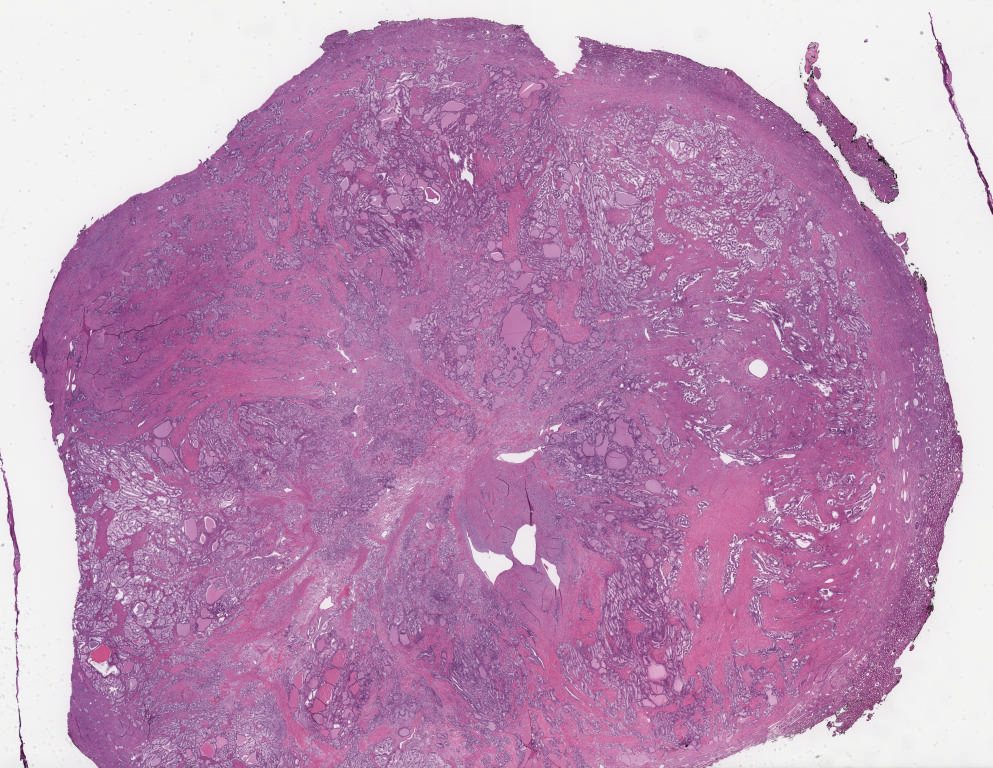

1161173.svs

40X